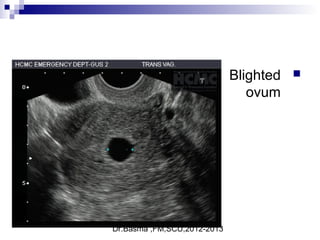

Blighted

ovum

 Transvaginal

ultrasound in a

longitudinal plane

showing a gestational

sac greater than 8

mm in diameter

without a yolk

Dr.Basma ,FM,SCU,2012-2013

Signs suggestive of abnormal embryonic developmentSigns suggestive of abnormal embryonic development

 include a gestational sac greater than 10 mm10 mm in diameter without a visible

yolk sac

 gestational sac greater than 18 mm18 mm in diameter without a fetal pole

 a collapsed gestational sac